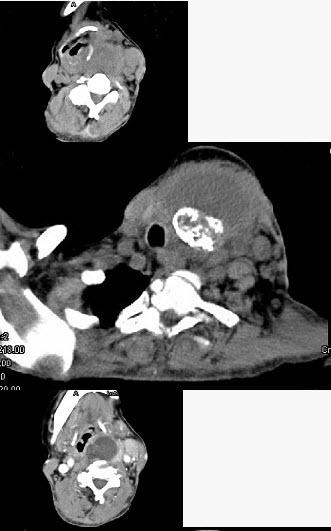

女,64岁,发现双甲状腺肿大一月余,CT如图所示,最可能诊断为()。

A、结节性甲状腺肿

B、甲状腺腺瘤

C、甲状腺癌并淋巴结转移

D、甲状腺转移癌

E、甲状腺结核

C